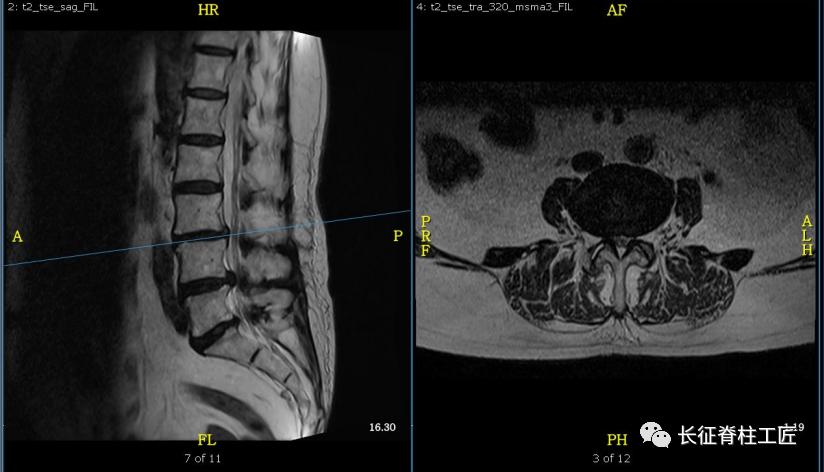

入院检查,腰部疼痛,后伸时加剧,局部压痛,双下肢肌力减退。X线检查,L4、L5骨质增生,MRI显示L4/L5、L5/S1椎间盘突出,马尾神经受压明显,被确诊为腰椎管狭窄症。

腰椎管是由前方的椎体后壁、椎间盘,侧方的椎弓根和关节突以及韧带,后方的椎板和黄韧带组成。这些组成部分增生肥厚或者椎间盘的突出,都可以造成中央椎管、神经根管或椎间孔处狭窄。